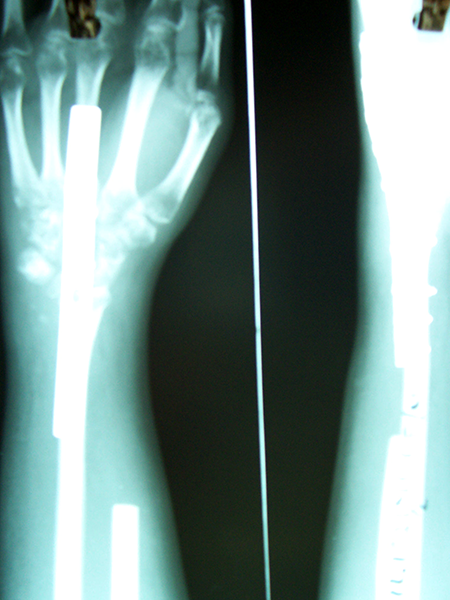

Case:2 GCT-L/E Radius

Pre-Op

Post-Op AP

Post-op Lateral